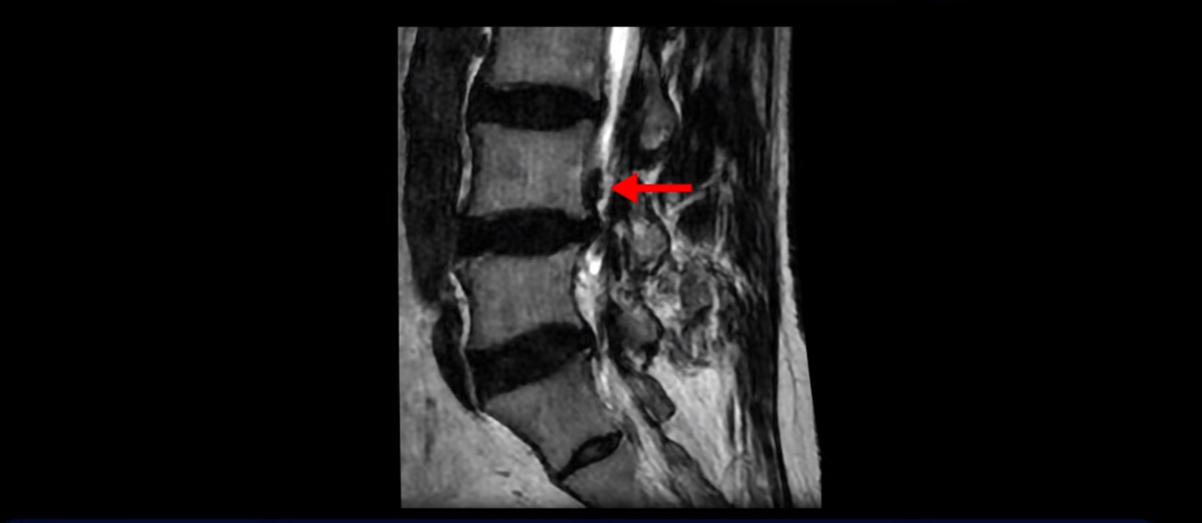

이분은 왼쪽 무릎 아래로 본인 표현으로는 다리를 잘라 버리고 싶다고 할 정도의 심한 통증이 있는데 보통 이런 표현은 디스크 파열이 발생했을 때 많이 사용하는 표현입니다. 이분 4번 5번 디스크를 자세히 보면 왼쪽으로 파열되어 밀려 올라간 디스크 수핵을 볼 수 있습니다.

20251020_4

옆에서도 보이지만 단면에서도 왼쪽으로 심하게 밀려나온 수핵이 잘 보입니다.